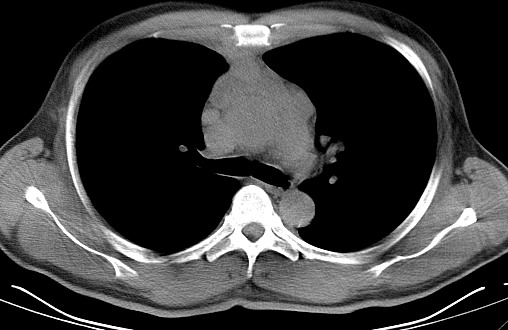

男   40   反复腹痛入院行彩超检查示胸骨右缘4、5肋间不均质回声团

淋巴瘤:前纵隔可见多组肿大的淋巴结,部分融合,有液化坏死